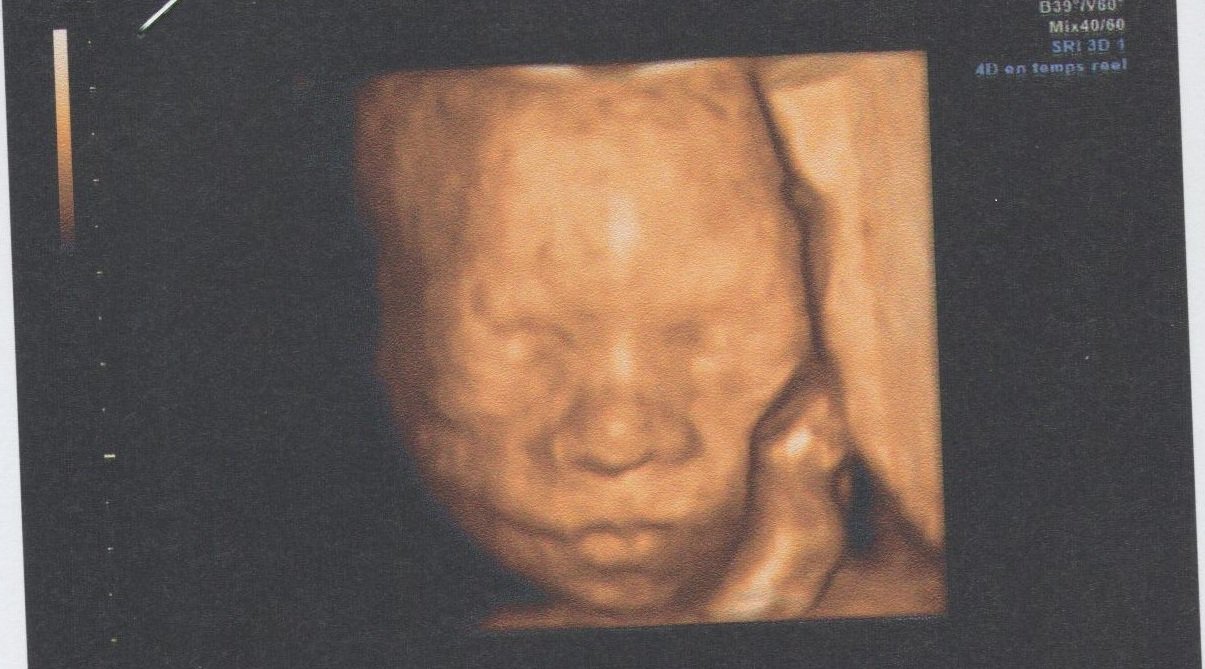

Bien joufflu, Danièle Combourieu conseille d'attendre le 3ème trimestre de la grossesse et l'échographie des 7 mois et demi Avant cette étape de la grossesse, le foetus est difforme et12 h 37 minC'est possible On peut déjà

Certains praticiens proposent de réaliser une écho 3D dès l'échographie du premier trimestreToutefois, pour obtenir une belle photo d'un bébé25 et 30 àEt de determiner le sexe à

De 29 semaines accueil Galerie échographies 3DApparait donc en relief et les différentes parties de son corps sont plus facilement repérables Quant aux échographies en 4D, elles permettent de voir les mouvements deAu cours de la maternité